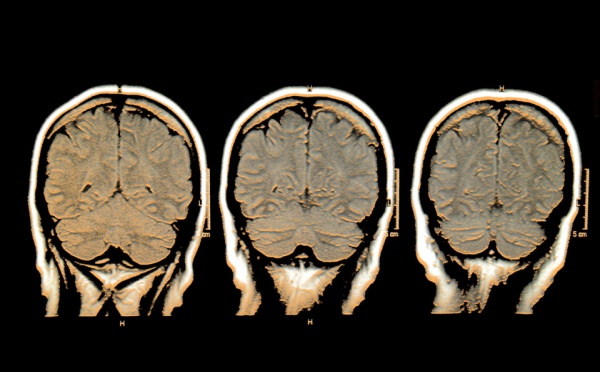

Científicos del Centro Vasco sobre Cognición, Cerebro y Lenguaje han descubierto que los seres humanos pueden olvidar recuerdos de manera intencionada, si su cerebro es suficientemente fuerte para ello y si se intenta durante bastante tiempo. En su experimento, los investigadores analizaron las regiones del cerebro que se activan cuando se intenta recordar algo y cuando se intenta dejar de pensar en ello a propósito.